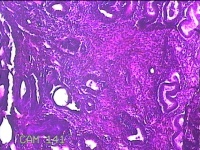

子宫腔赘生物(大)

性别

女

年龄

38岁

临床诊断

子宫内膜息肉;子宫异常出血

一般病史

月经量多数年,发现宫腔占位1个月。

标本名称

大体所见

灰白暗红色不规则肿物2.7x1.8x0.8cm一堆,切开肿物呈实性,切面灰白暗红色,质软。

有那么点像子宫内膜息肉,片子这个效果,辩认起来非常困难。